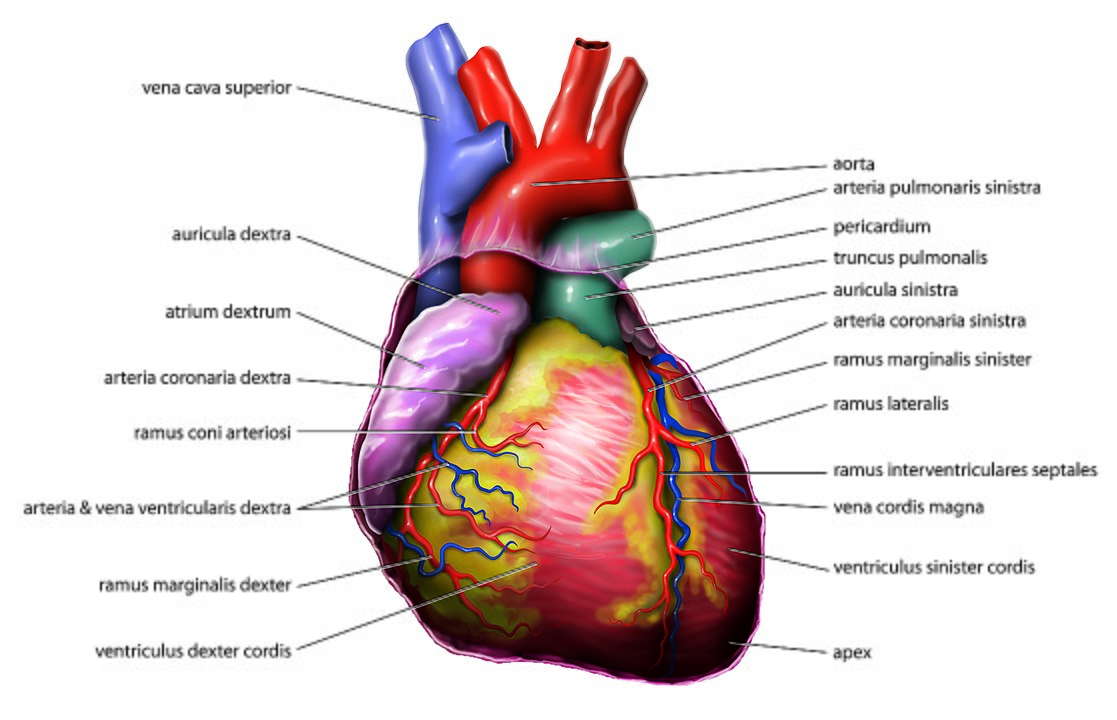

|

| Anatomie des Herzens | EKG-Komponenten einer Herzperiode |